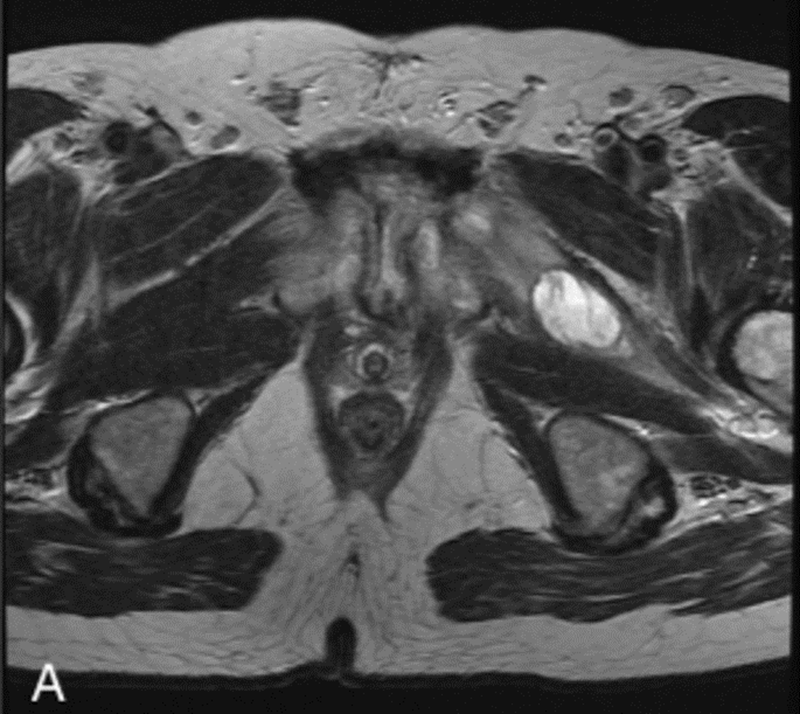

图3.核磁共振显像